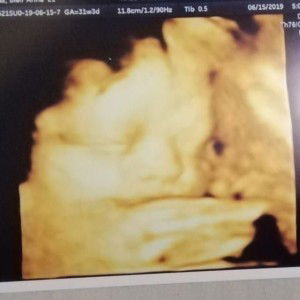

mga momsh bakit kaya sumasakit balakang ko? natural kaya to? 37weeks and 1day nako.

yes po normal. pero bantayan po signs ng labor